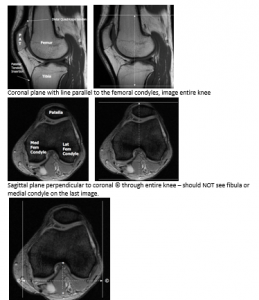

Knee

Coronal plane with line parallel to the femoral condyles, image entire knee

Sagittal plane perpendicular to coronal © through entire knee – should NOT see fibula or medial condyle on the last image.